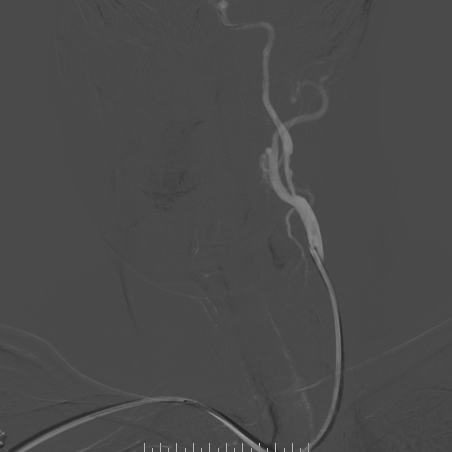

超声及超声造影

-- 左侧颈内不规则低回声,新生血管分级:IV级,提示为易损斑块

-- 右侧颈内不规则混合回声,表面钙化为主,新生血管分级:III级